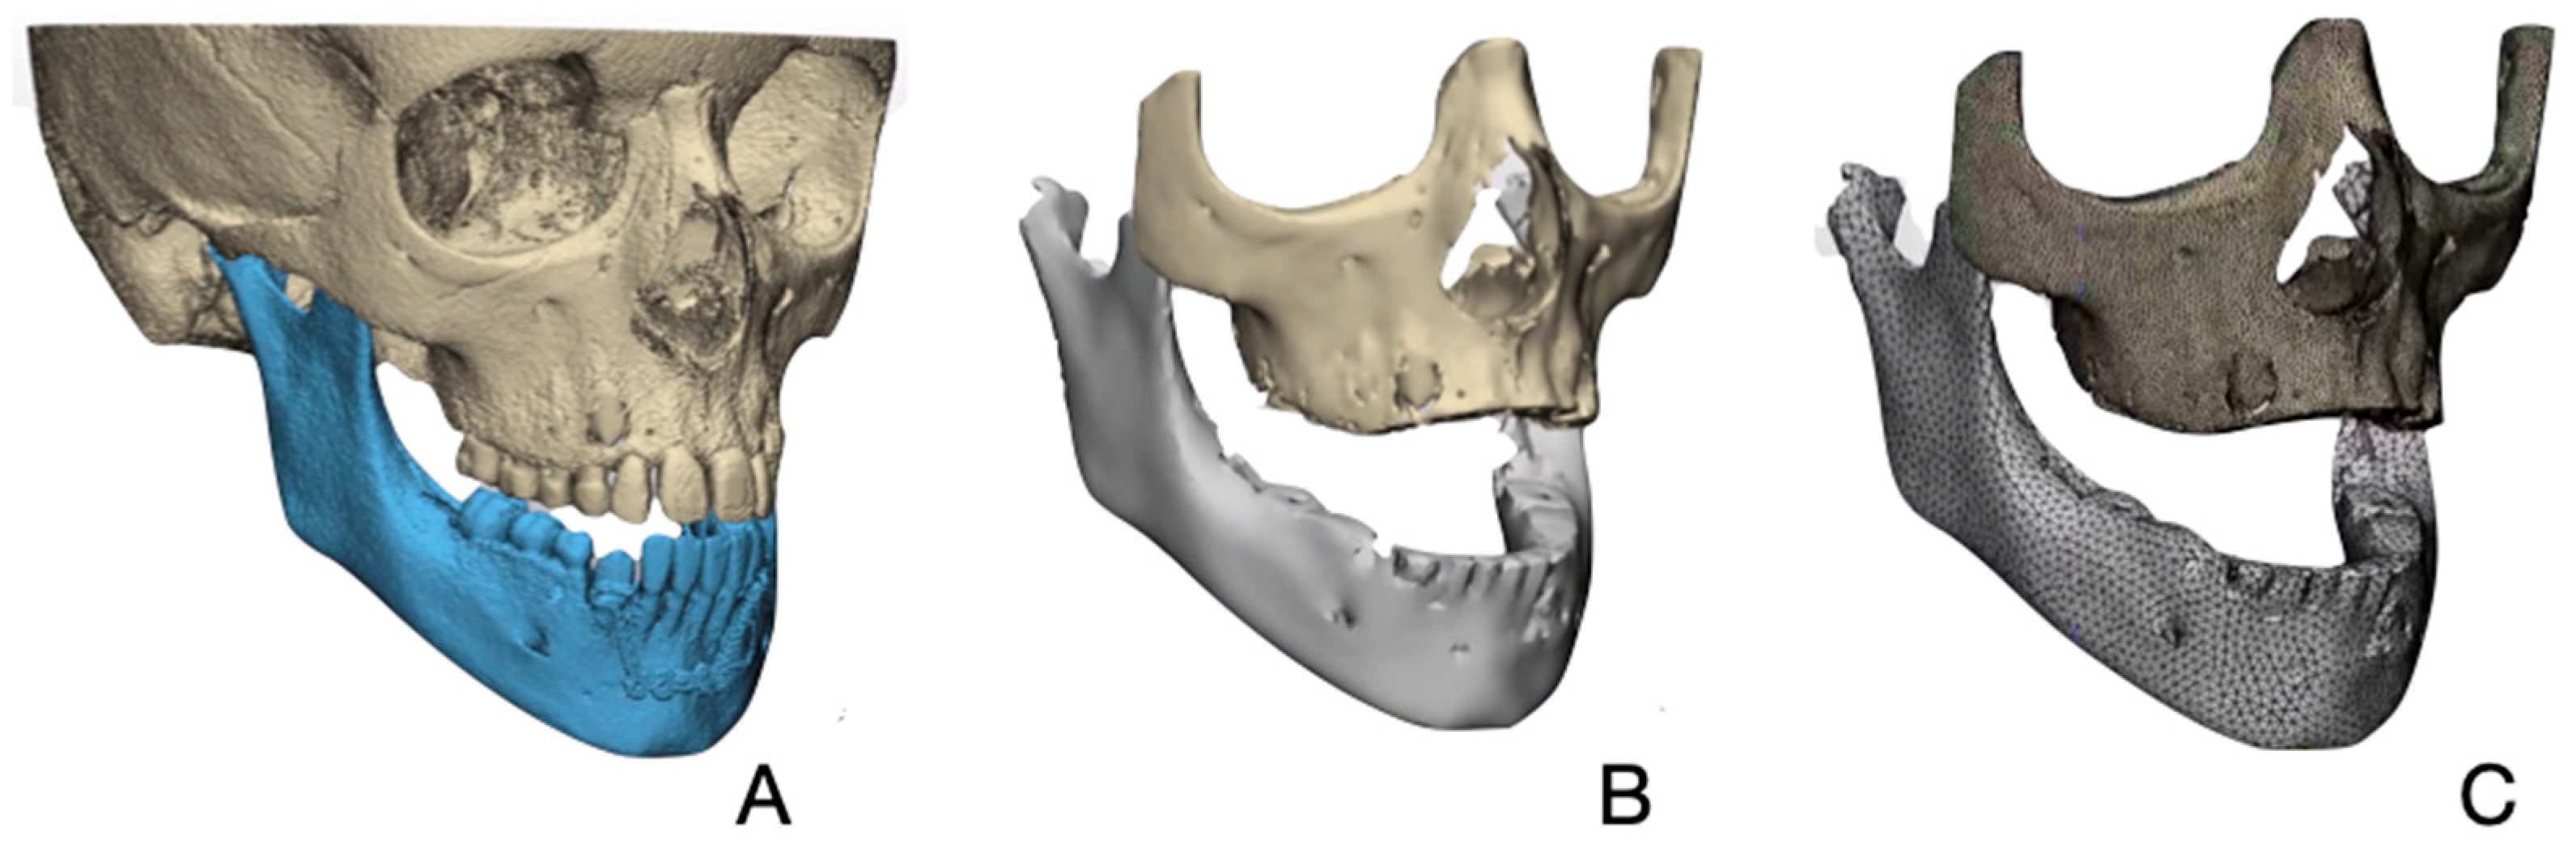

2.3. Creating a Patient Specific 3D FE Model

2.4. Finite Element Analysis (FEA)

2.5. Boundary Conditions